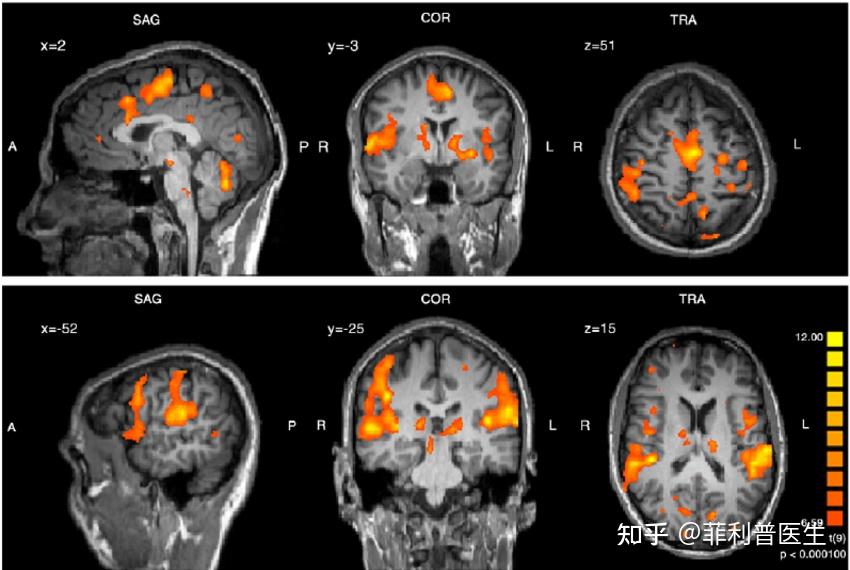

磁共振还有一个最大的好处,就是丰富的扫描序列,可以透露出组织内部更加丰富的细节,甚至可以识别出精细解剖结构、炎症、水肿、组织微观损伤、血液灌注和血管造影。甚至可以通过检测大脑活不同部位血氧水平变化来间接得到哪个脑区正处于活跃状态,从而追踪一个人的情绪、记忆、支配肢体等多种大脑活动,也被称为功能磁共振(fMRI)。

同时,时间分辨率也能够提高:高磁场强度可以缩短数据采集时间,从而提高时间分辨率。这对于动态研究和功能性磁共振成像(fMRI)等需要高时间分辨率的应用非常重要,可以更准确地捕捉到生物过程的快速变化。电光火石之间的脑活动变化也有可能被捕捉到。